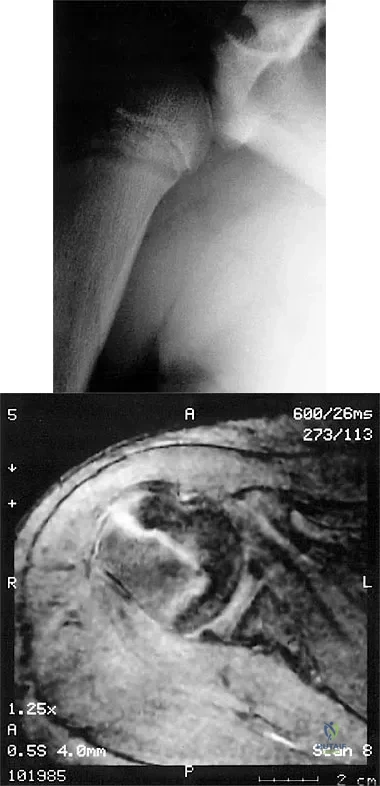

A 14-year-old boy sustains a twisting injury to his right shoulder and recalls feeling a snap during a wrestling match. Examination shows hesitancy to raise the arm away from the side, diffuse tenderness and swelling of the upper arm, and no evidence of neurovascular compromise. Figures 6a and 6b show an AP radiograph and MRI scan. What is the most likely diagnosis?